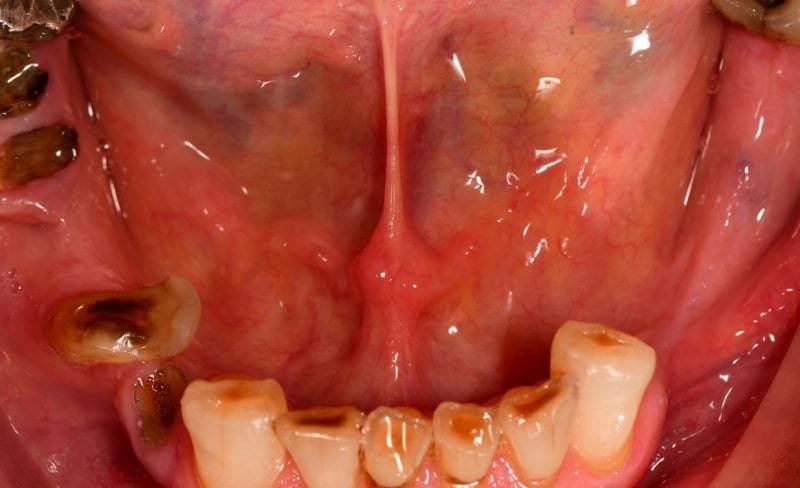

Upper and lower all-on-4 dental implants to restore function and aesthetics.